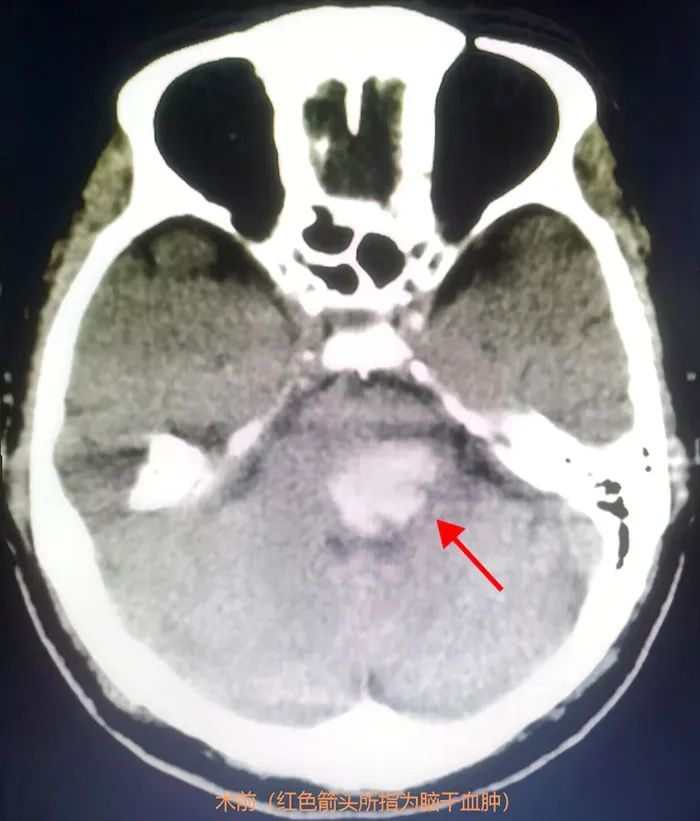

▲患者术前影像

71岁的巫爷爷因突发神志不清伴呕吐至我科住院,行颅脑CT检查提示桥脑出血量约6ml。在神经外科学科带头人王鹏指导下,神经外科杨建雄主任、郑达理副主任医师等神经外科一区团队经过术前讨论分析,结合家属意愿,制定了机器人手术方案,从血肿定位及靶点确定、手术路径规划设计,结合患者的CT影像数据,设计出最优的手术路径,在此基础上进行后期人工微调以进一步减少手术风险和对正常脑组织的损伤,成功为患者实施机器人辅助立体定向脑干血肿清除术。

术后8小时复查颅脑CT示引流管位置精准、脑干血肿基本清除,48小时内成功拔管。